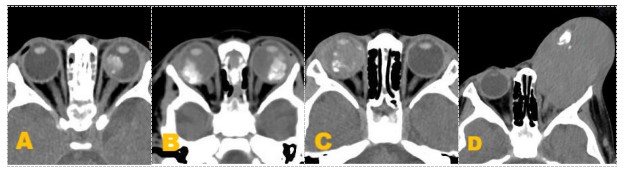

图3 分期影像特征示图

Figure 3 Diagram of staging CT imaging features

图3分期影像特征示图